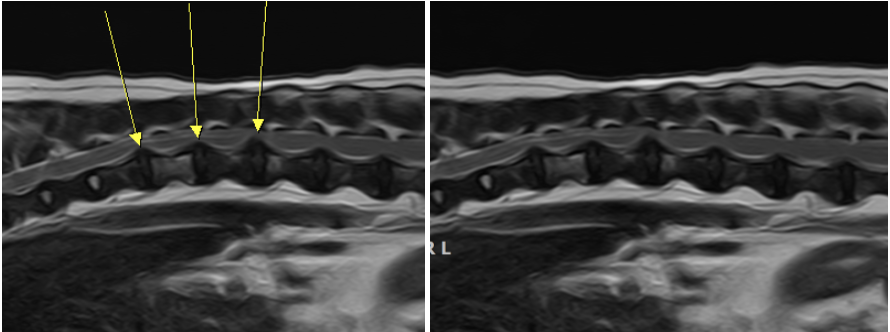

MRI검사를 통해 흉요추 디스크 문제가 원인으로 확인되었습니다.

다발성 흉요추 부위 디스크문제가 확인되었고, 현재 증상을 나타내는 부위를 정확히 진단하기 위한 평가가 진행되었습니다.